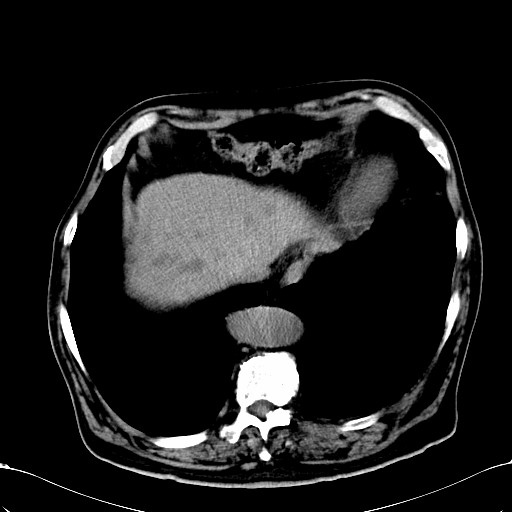

标题: CT28270:胰管扩张,肝多发占位 [打印本页]

标题: CT28270:胰管扩张,肝多发占位

患者,男,75岁。

考虑胰腺钩突癌并肝内转移,建议强化明确。

1)考虑胰头癌并肝脏多发性转移;建议行ct增强扫描检查。2)胃窦癌?建议行胃镜检查。

胰管有扩张,位置比较低,同意楼上几位高手意见。肝内转移可能大,建议增强。

肝脏多方低密度结节,边缘模糊,考虑多发转移,胰管明显扩张,建议增强扫描钩突情况